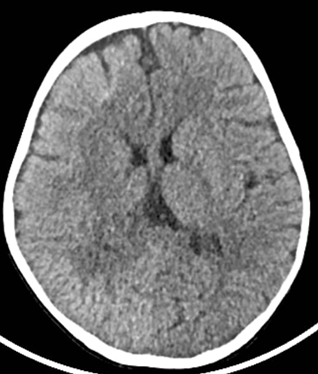

We report in this paper the picture of a child K, male, 1-year-old, weighing 9 kg, received at the neuropsychiatric center. Born at term, normal delivery with a birth weight of 4,100 kg. One day later, he was put in an incubator without oxygenation. He is the 7th in a family of 7 children with a history of malformation reported in the family or epileptic seizures. Her mother reports regression in milestone (speech and walking). On examination, we find cranial dysmorphism made up of an asymmetrical head with the right hemiface more prominent than the left (Figure 1), right hemicorporal erythroderma from head to foot taking the inner and posterior face (Figure 1) and describing an atypia by taking half of the sole of the right foot (Figure 2) while the left hemibody is of normal colour. There are left hemicorporal tonic-clonic convulsive seizures which become generalized secondarily and are undergoing. A treatment consisting of valproic acid syrup at 30 mg/kg and injectable dexamethasone at 1 mg/kg made it possible to control the attacks after a failure of treatment with phenobarbital which was administered at the referral hospital. A performed sleep EEG showed spikes and some wave spikes localized to the rigth hemisphere, A performed cerebral computed tomography shows on an axial section a cerebral hemiatrophy of the right hemipshere (Figure 3) with a double cerebral cortex in the frontal region and polymicrogyria (Figure 4). A basic biological assessment carried out and not contributory.

Figure 3 Right cerebral hemispheric hemiatrophy.

The hemiatrophy of the right cerebral hemisphere in our patient proves a complete migration of neurons to the definitive site, but the lack of development or maturation would explain this cerebral anomaly. And therefore, this would be neither of inflammatory origin as in Rasmussen's encephalitis which constitutes a differential diagnosis, nor of degenerative origin.